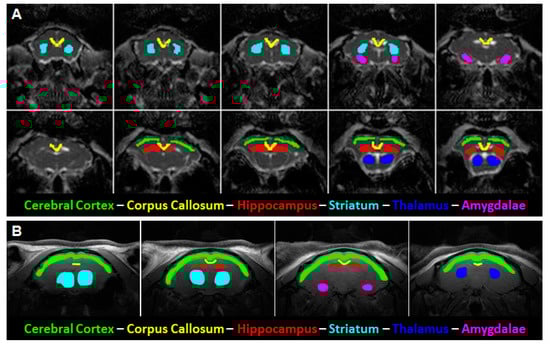

2.3. Data Processing

3.3. Age Dependence of Regional FA

3.4. Age Dependence of Regional Diffusivity Measures

3.5. Age Dependence of Regional Kurtosis Measures

3.6. Age Dependence of Regional T2 Relaxation Time